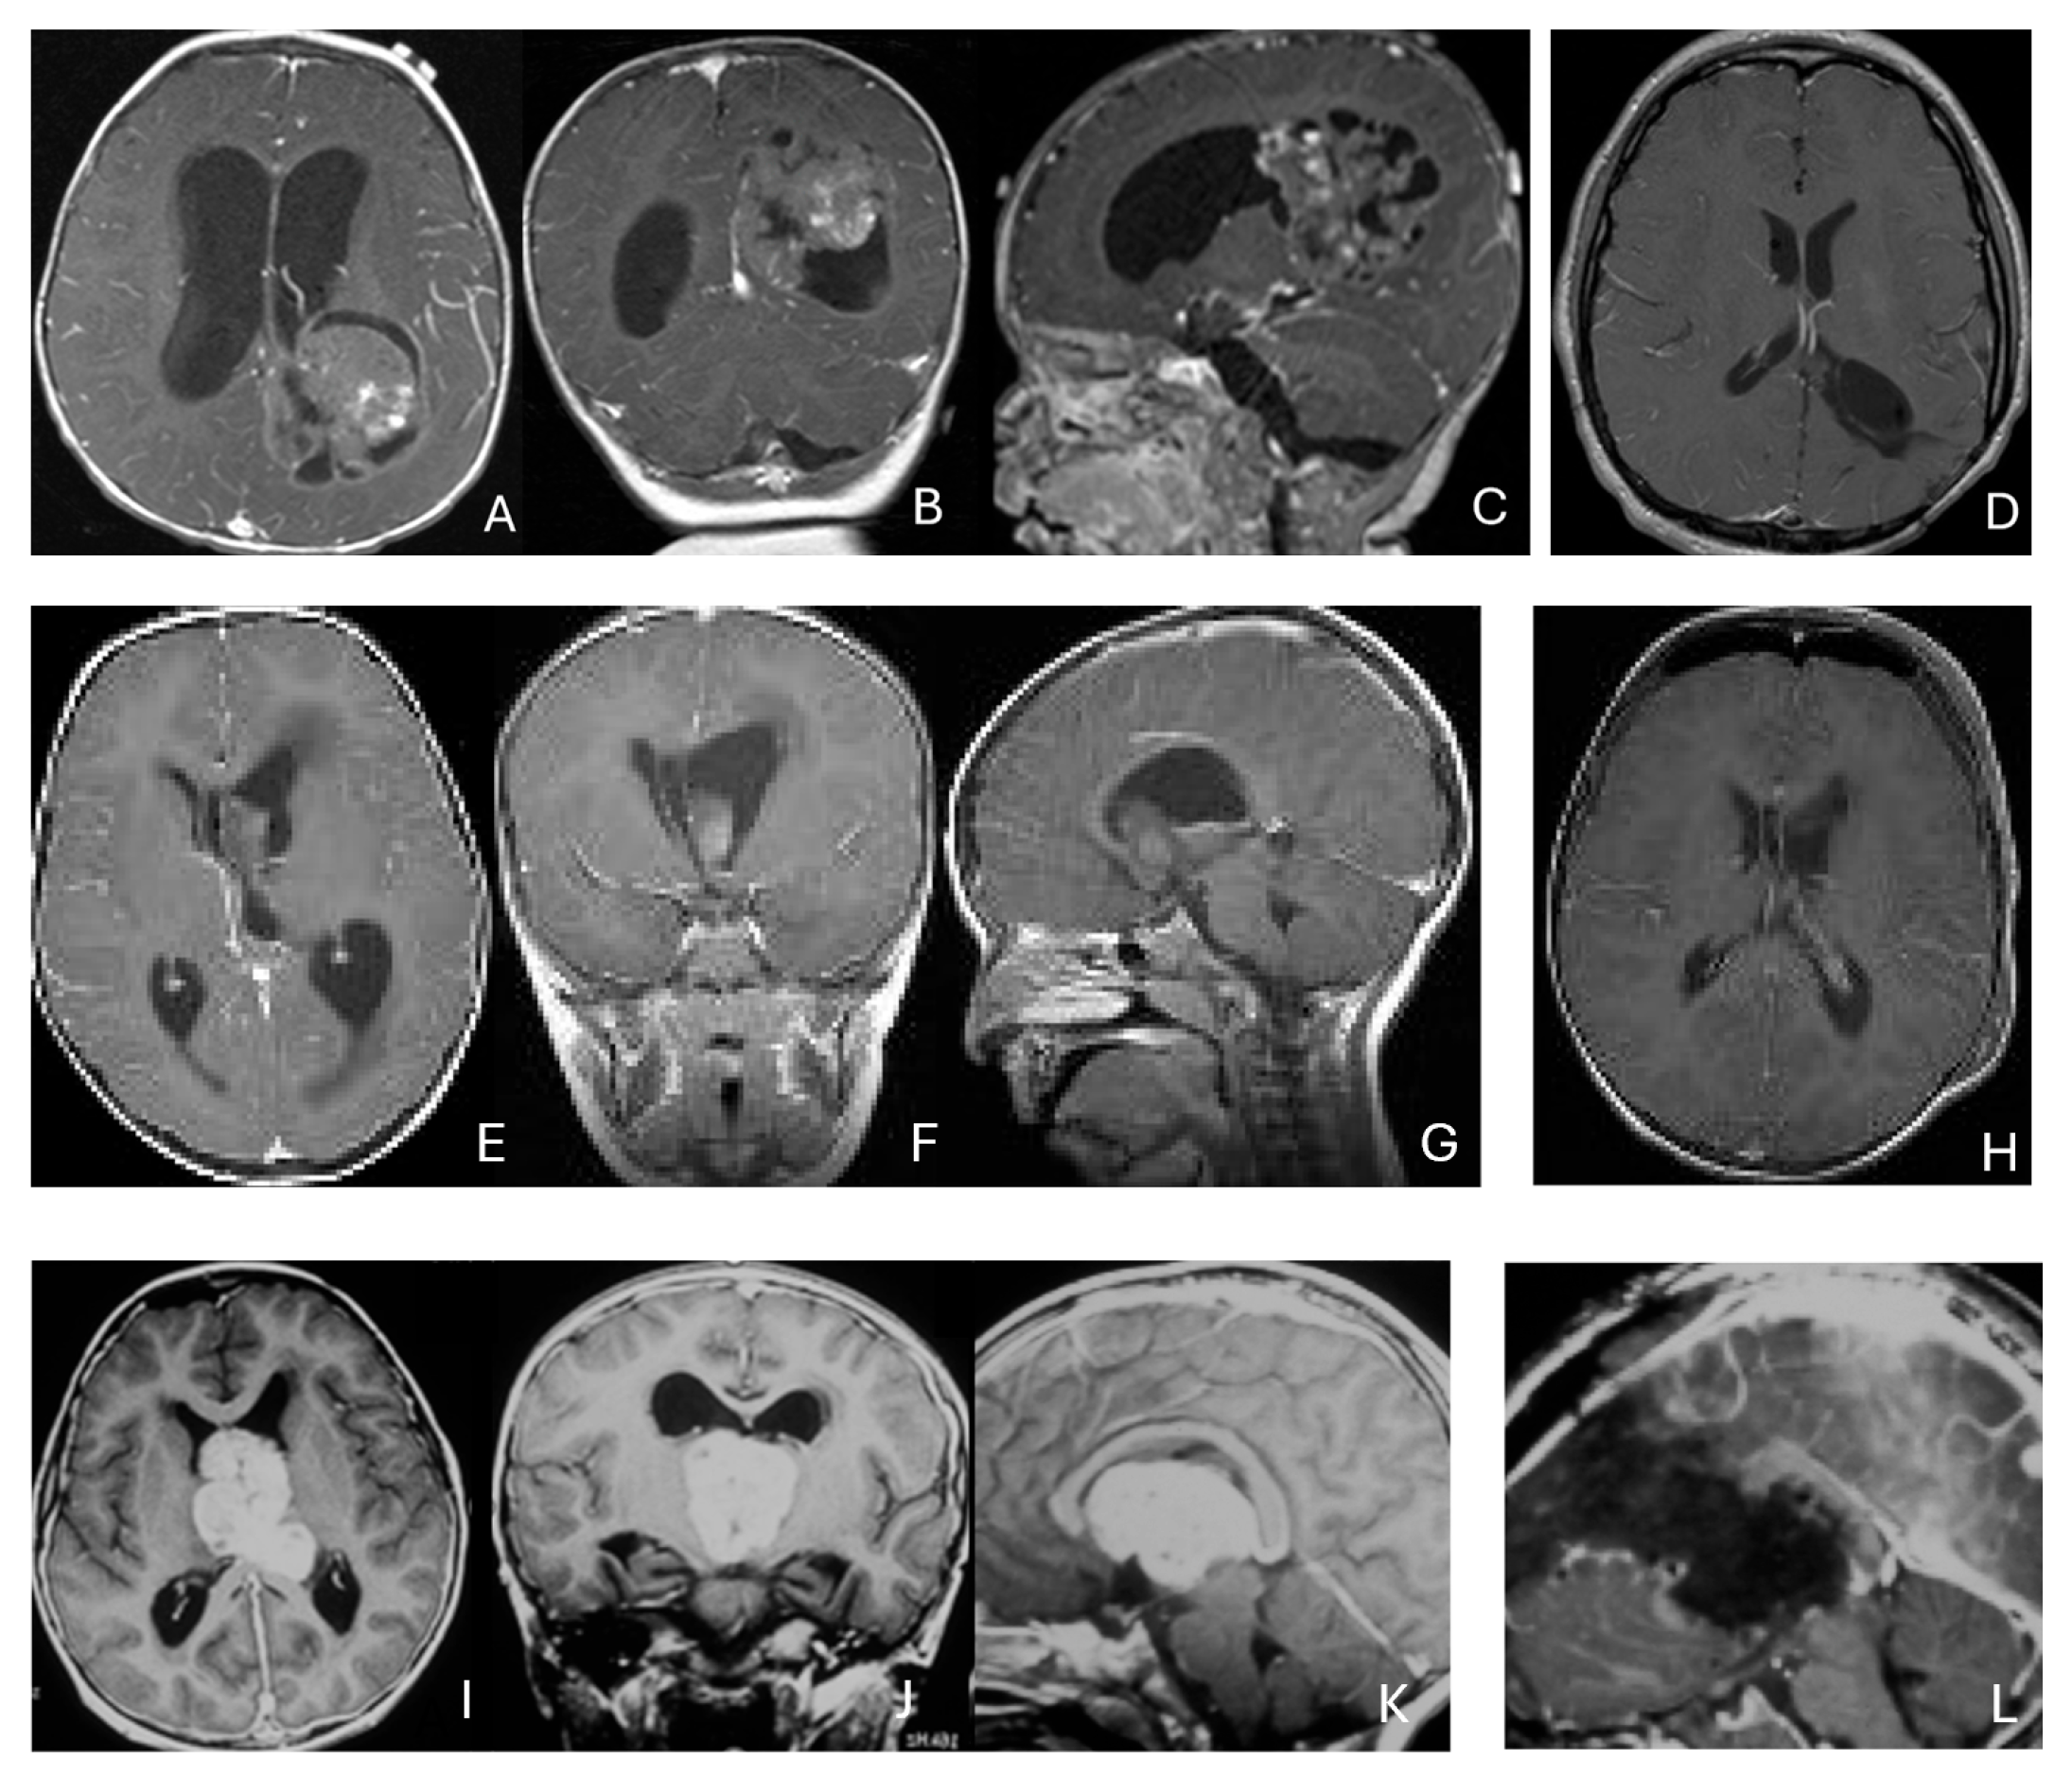

Tumor epicenters and patterns of extension were best delineated by operative observations combined with preoperative and postoperative imaging (Figure 1). Three patients had tumors involving both the temporal and frontal lobes that crossed the Sylvian fissure (Figure 2). Despite appearance of thalamic involvement on preoperative imaging, two patients had tumors primarily occurred in the basal ganglia, which became more evident on postoperative MRI (Figure 3). Additional hemispheric tumor extended into the thalamus. These lesions were resected via a trans-sylvian approach.

Figure 1.

Cerebral lobar ATRT. (A–D): 20-month-old boy with a parietal intraparenchymal ATRT. Preoperative axial images (A,B) and postoperative axial (C) and coronal (D) images confirm the intraparenchymal location following resection. (E–H): 26-month-old boy with a large heterogeneous frontal mass with multiple peritumoral cysts. Preoperative axial (E) and coronal (F) images, and postoperative axial (G) and coronal (H) images after gross-total resection support a frontal lobe origin despite of the basal ganglia origine as the preoperative imaging suggetsed.

Figure 2.

Multi-lobe ATRT. (A–D): A 3-year-old boy with a heterogeneous frontotemporal ATRT with encasement of Sylvian vessels on MR images ((A), axial; (B), coronal). Intraoperatively, the tumor replaced both the frontal and temporal opercula, extended to the anterior, and displaced/encased branches of the middle cerebral artery. Postoperative MR images after resection ((C), axial; (D), coronal) confirm multilobe involvements. (E–H): of a 30-month-old boy with a temporoparietal cystic ATRT crossing the Sylvian fissure shown on T2-weighted MR images ((E), axial; (F), coronal). Correlative intraoperative findings and imaging demonstrated the tumor extending from the temporal lobe into the posterior frontal lobe across the Sylvian fissure and encasing middle cerebral artery branch. Post-resection MR images ((G), axial; (H), coronal) show a resection cavity spanning the temporal and posterior frontal opercula.

Figure 3.

Basal ganglia ATRT. (A–D): Post contrast MR images ((A)-axial, (B)-coronal) of 13-month-old boy with deep seated ATRT. Note the solid tumor with peritumoral cysts at the basal ganglia with one cyst extending to the thalamus. Post-resection MR images ((C)-axial, ((D)-coronal) show the tumor resected cavity in the basal ganglia with the thalamus clear of tumor involvement. (E–H): Post contrast MR images ((E)-axial, (F)-coronal) of a 23-month-old boy with a large ATRT of deep temporal lobe and the insula extending to the basal ganglia. The tumor was predominantly in the basal ganglia as shown postoperative MR ((G)-axial, (H)-coronal).

Three tumors were predominantly located within the ventricle, two within the lateral ventricle and another within the third ventricle (Figure 4). None appeared to arise from the choroid plexus or as pedunculated lesions from the ependymal layer; rather, operative and imaging features supported a paraventricular origin because of diffuse attachment to the ventricular wall. Two large hemorrhagic hemispheric tumors extended into the lateral ventricle. These paraventricular ATRT extends into the lateral ventricle (Figure 5).

Figure 4.

Intraventricular ATRT. (A–D): A 7-month-old boy with ATRT within the left lateral ventricle with associated hydrocephalus shown on MR images ((A), axial; (B), coronal; (C), sagittal). Note irregular peritumoral cysts and ependymal invasion which was confirmed at surgery. Postoperative MR image ((D), axial) shows a gross-total resection. The patient had a history of rhabdoid tumor predisposition syndrome. (E–H): A 34-month-old boy with MR images ((E), axial; (F), coronal; (G), sagittal) showing an intraventricular mass at the anterior horn based on the septum pellucidum. ATRT was originated at the junction of the septum pellucidum. Post-contrast MR ((H), axial) confirms resection. (I–L): Post-contrast MR images ((I), axial; (J), coronal; (K), sagittal) of a 3.5-year-old boy demonstrate a large, enhancing third ventricular ATRT with partial extension into the lateral ventricle. The lesion was removed via an interhemispheric transcallosal approach ((L), sagittal).

Figure 5.

Paraventricular ATRT with ventricular extension. (A–D): A 3-month-old girl who presented with emesis followed by acute decerebrate posturing. Post-contrast MR images ((A), axial; (B), coronal; (C), sagittal) reveal a large hemorrhagic mass in a deep centrencephalic location. Postoperative MR ((D), axial) shows a focal dilation of the lateral ventricle after subtotal resection of a parietal para-ventricular ATRT.

Three patients presented with massive subdural/parenchymal masses involving both cerebral hemispheres across the falx cerebri; two bi-frontal and one in bi-occipital (Figure 6). These tumors appeared to originate within the cerebral hemispheres and permeate or traverse the falx cerebri, resulting in bilateral disease.

Figure 6.

Bi-hemispheric ATRT. (A–E): MR images ((A), axial; (B), coronal; (C), sagittal) of a 4-year-old boy show a bifrontal ATRT crossing the falx cerebri, with heterogeneous enhancement. The corpus callosum is compressed posteriorly. At surgery, left frontal component invades and permeates through the falx with extension into the right subdural space. Postoperative images after bifrontal craniotomy ((D), axial; (E), coronal) show tumor resection. Bi-occipital hemispheric ATRT. (F–J): MR images ((F,G), axial; (H), coronal) of a reveal a 22-month-old girl large, inhomogeneous left occipital lobe mass crossing the midline into the right occipital lobe. The lesion invades the posterior falx cerebri and extends into the medial occipital lobe of the right side. A highly vascular tumor was resected via a left occipital craniotomy; the right occipital component was not removed with concern of blindness due to preexisting right homonymous hemianopia. She received chemoradiation with durable disease resolution for over 15 years, as shown on follow-up post-contrast MR ((I), axial; (J), coronal).

Of the supratentorial tumors, 8 were solid and 7 demonstrated peritumoral cysts. Five showed signs of central necrosis, and 2 had intratumoral hemorrhage with associated intraventricular hemorrhage. Additional hemorrhagic foci were identified on susceptibility-weighted or gradient-echo sequences in others. Post-contrast MR imaging demonstrated heterogeneous enhancement following contrast infusion with variable degrees. Diffusion-weighted imaging uniformly showed restricted diffusion.